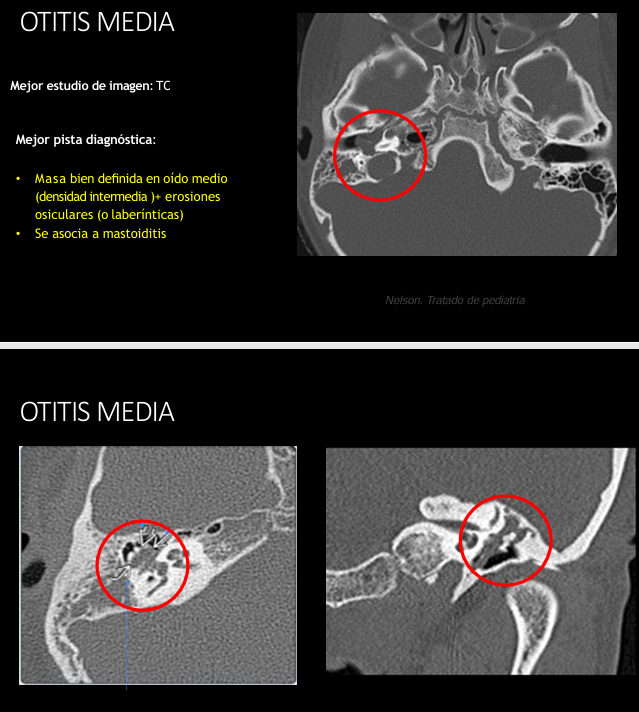

Tc en otitis media

Masa bien definida en oído medio (densidad intermedia)

Erosiones osiculares o laberínticas

Asociación a mastoiditis